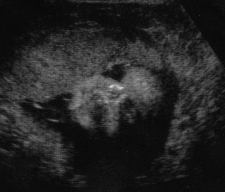

Pregnancy at 28 Weeks

Another close up side view.

Look at those feet all curled up.